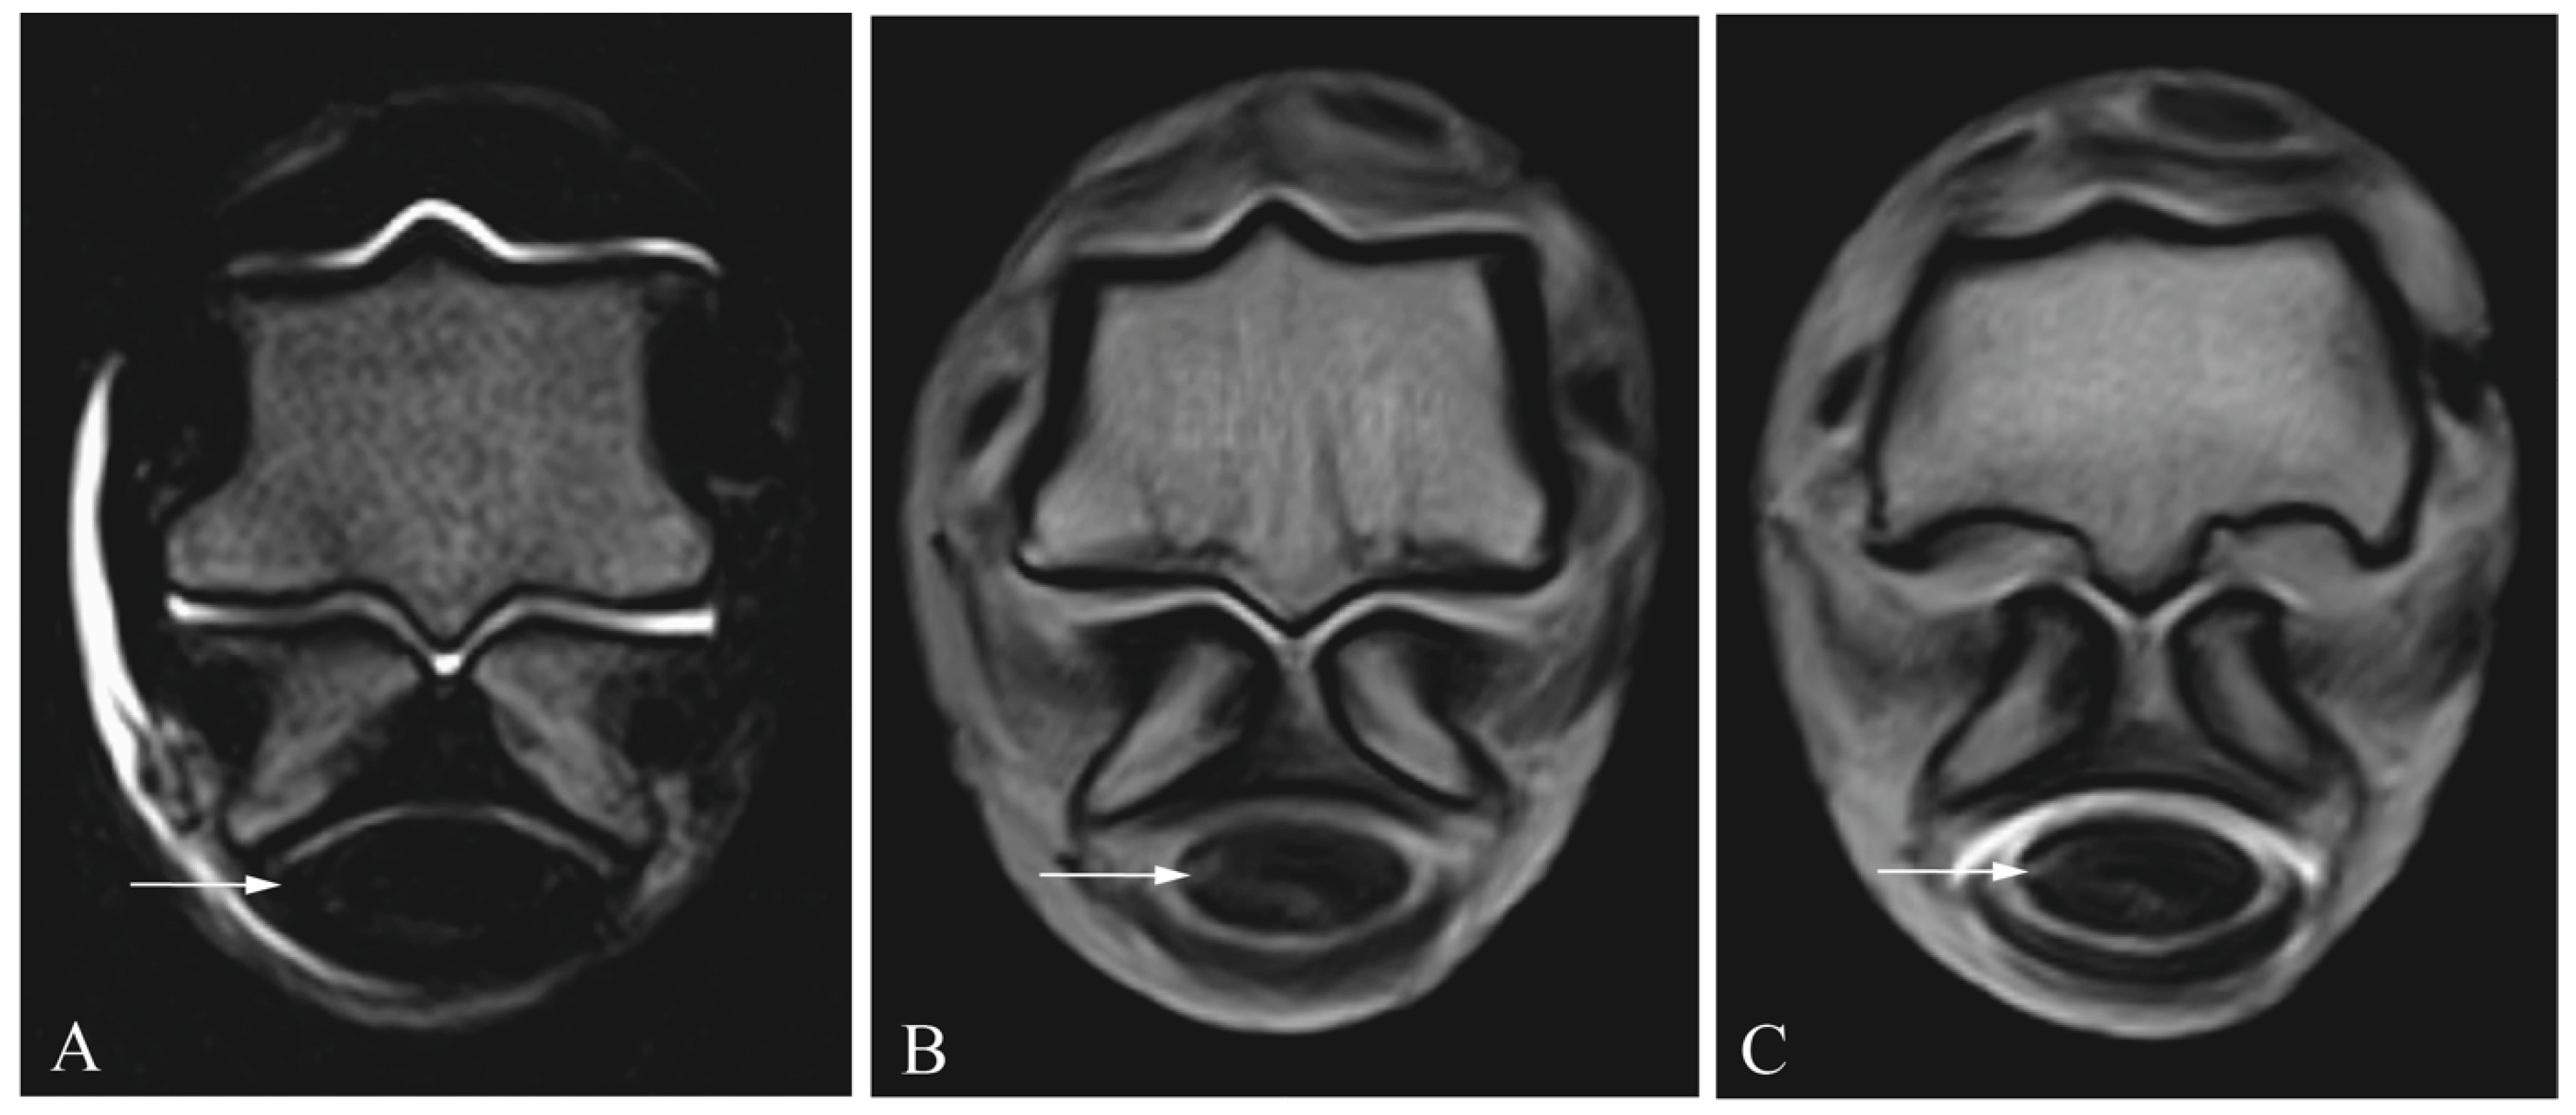

2.2. Tenoscopic Procedure

2.3. Diagnostic Imaging

2.4. Image Analysis